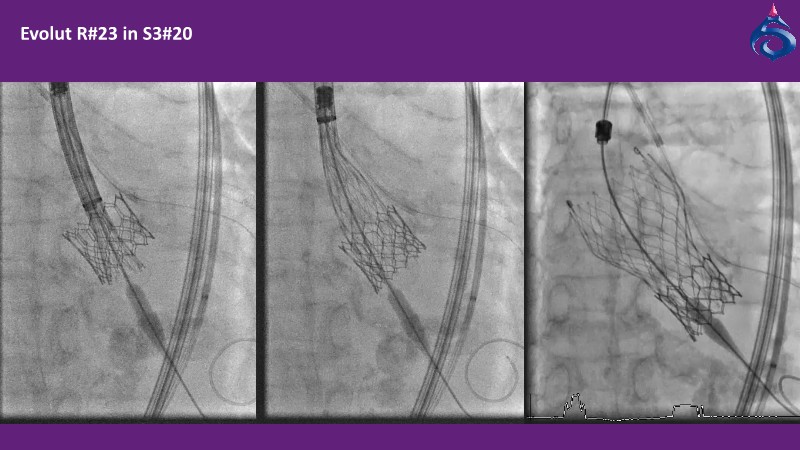

Watch this expert-led session on the latest Evolut TAVI advancements, device selection for small annulus cases, and strategies for complex anatomies. Learn about redo-TAVI feasibility and key 1-year data from the SMART trial.

• To master implantation techniques and discern the latest technological evolutions for treating patients with complex anatomies